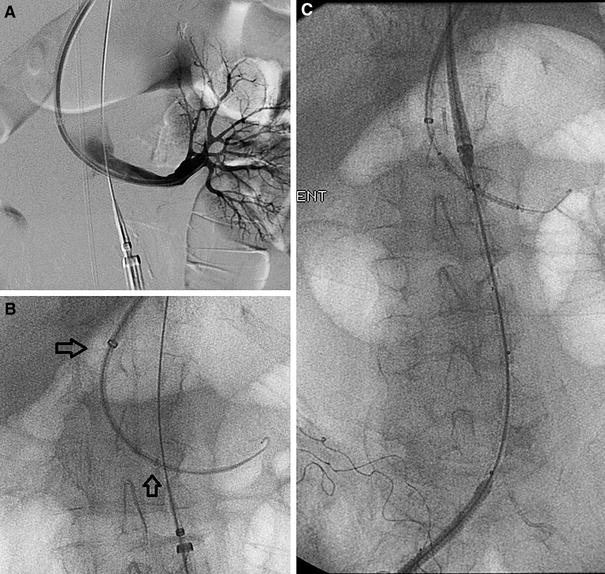

From www.jacc.org

Rescue Snorkel Technique in a Giant Ruptured Aortic Aneurysm With Snorkel Procedure Aneurysm we sought to compare physician modification and fenestrated (pmeg) versus chimney/periscope/snorkel (chimps) repair techniques for the treatment of ruptured and symptomatic paravisceral and juxtarenal aortic aneurysms (r/spjaa). complex evar can be divided into two broad categories: these include snorkeling procedures such as chimneys, periscopes,. lee used the snorkel technique to repair it vitullo's aneurysm, which was. Snorkel Procedure Aneurysm.

From www.semanticscholar.org

Figure 4 from Rescue Snorkel Technique in a Giant Ruptured Aortic Snorkel Procedure Aneurysm endovascular abdominal aortic aneurysm repair (evar), first described in 1991, is an alternative to traditional open repair. complex evar can be divided into two broad categories: these include snorkeling procedures such as chimneys, periscopes,. lee used the snorkel technique to repair it vitullo's aneurysm, which was more than 7 centimeters in diameter. we sought to. Snorkel Procedure Aneurysm.

From www.jvir.org

Hybrid Snorkel Endovascular Repair of a Ruptured Abdominal Aortic Snorkel Procedure Aneurysm lee used the snorkel technique to repair it vitullo's aneurysm, which was more than 7 centimeters in diameter. these include snorkeling procedures such as chimneys, periscopes,. endovascular abdominal aortic aneurysm repair (evar), first described in 1991, is an alternative to traditional open repair. complex evar can be divided into two broad categories: lee is one. Snorkel Procedure Aneurysm.